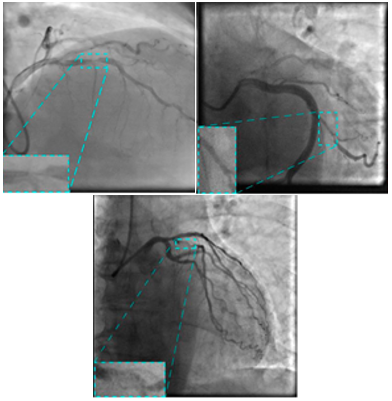

The image dataset utilized in this study was sourced from a publicly available repository provided by Danilov et al. [9]. The images, similar to those given in Figure 2, were captured using high-end imaging systems, namely the Coroscope (Siemens) and Innova (GE Healthcare), which are widely used in clinical practice for precise visualization of coronary arteries.

The dataset comprised angiographic scans from 100 patients, each of whom had been clinically diagnosed with single-vessel coronary artery disease, either through functional assessments or direct angiographic evaluation. The dataset featured a total of 8,325 grayscale images, with resolutions ranging from 512×512 to 1000×1000 pixels, ensuring detailed visualization of the vascular structures. These high-quality images provided an excellent basis for training and evaluating deep learning models, particularly for detecting stenotic regions. Details of each step employed for detecting CAS from XCA images are provided below and are depicted in Figure 3.

Figure 2. Sample angiography images included in the data set [9]